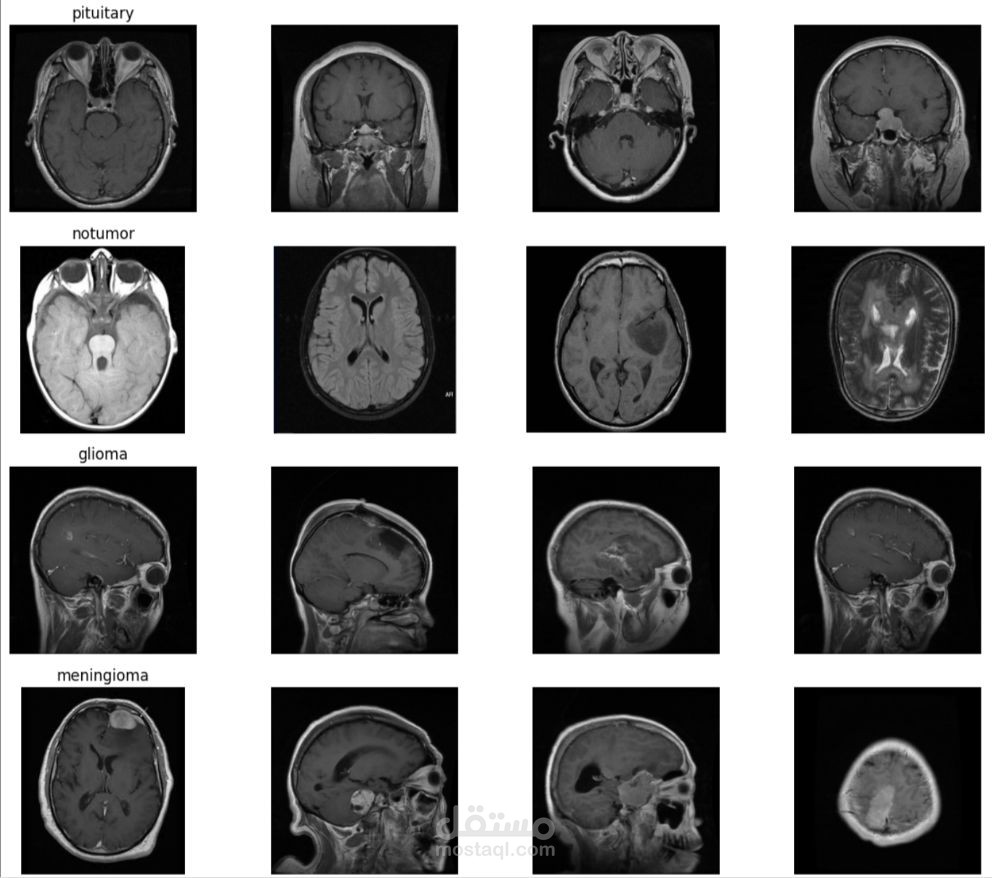

Using MRI scans as input, my model can predict whether a brain tumor is present. This can help radiologists and doctors save time and focus on the critical decision-making process.

Data Preparation: Preprocessed MRI images (resizing, normalization, augmentation) to improve model generalization.

Deep Learning Model (PyTorch): Designed a Convolutional Neural Network (CNN) with Conv2D, MaxPooling, Dropout, and Fully Connected layers.

Evaluation: Measured accuracy, precision, recall, and F1-score, and created a confusion matrix for better insights.

Results: Achieved high performance and demonstrated the potential of AI in medical imaging.